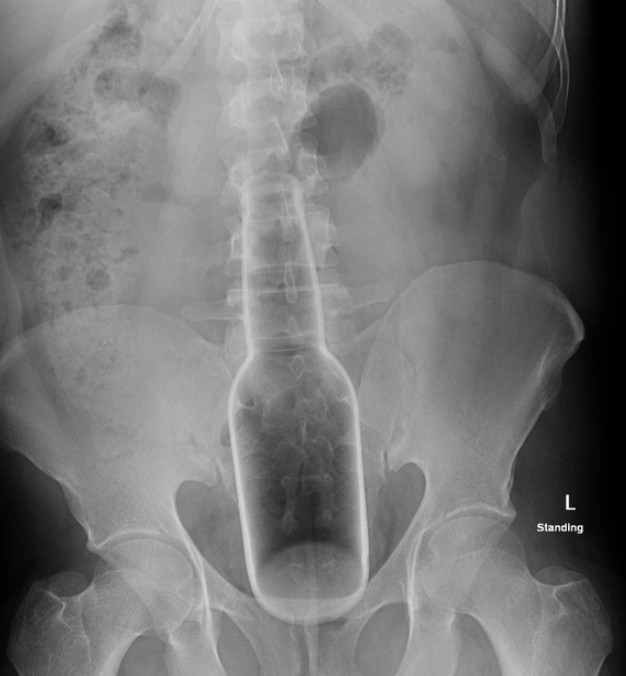

Den Rekord hält ein Kerl, der es geschafft hat sich eine Bierflasche (0,5l) derart in den Hintern zu schieben, dass sie von außen nicht mehr zu sehen war und operativ entfernt werden musste. Ich habe bei dem Eingriff assistiert. Die Flasche hatte sich am Übergang vom Sigma zum absteigenden Colon des Dickdarmes verkeilt und hätte die Darmwand fast aufgerissen.

bier.jpg

Es gab auch schon Fälle bei denen das Glas-Spielzeug in Aktion zerbrochen ist. Das kann dann lebensgefährliche Folgen haben. Deswegen immerl den Kopf benutzen bevor das Köpfchen die Regie übernimmt